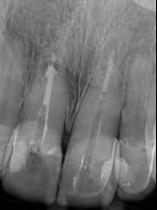

Dientes 31 y 41 - Reabsorción Interna / Conducto obturado con BIO-C® REPAIR. Imágenes cedidas por la Dra. Cimara Barroso.

Tratamiento de reabsorción interna vía conducto

1. Anestesie e instale el aislamiento absoluto;

2. Quite el tejido de granulación del área de la reabsorción;

3. Haga la neutralización del medio con BIO-C® TEMP;

4. Quite el BIO-C® TEMP en la siguiente sesión y haga el tratamiento endodóntico de la manera convencional hasta la altura de la reabsorción;

5. Aplique el BIO-C® REPAIR en el lugar de la reabsorción, condensándolo contra las paredes con instrumentos específicos o una bolita de algodón estéril ligeramente humedecida;

6. Realice el sellado coronario con ionómero de vidrio y restauración con el material de preferencia;

7. Radiografiar y hacer el seguimiento por lo menos dos años.